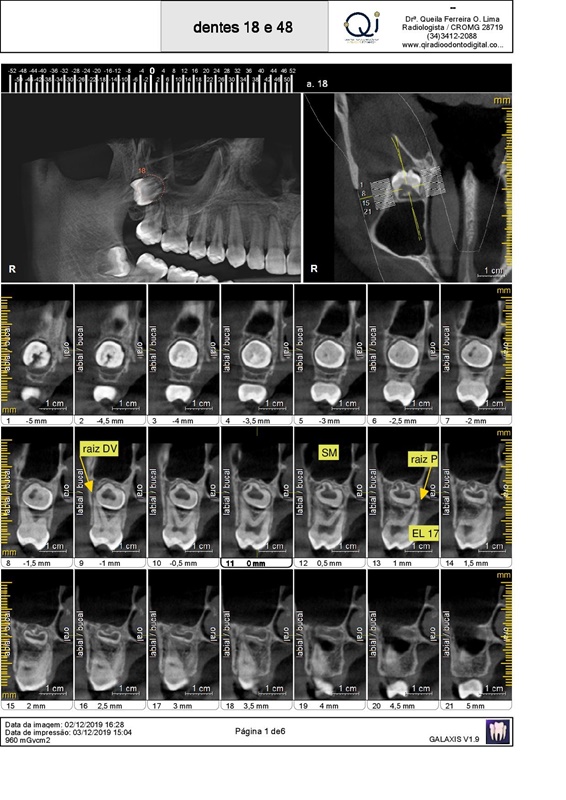

Tomografia Volumétrica:

- ATM

Boca aberta/semiaberta/fechada

- Cirurgia Oral

Dente incluso e/ou supranumerário

Terceiros molares, posicionamento e/ou relação com o canal mandibular/seio maxilar

Patologia

- Endodontia

Pesquisa de dilaceração/perfuração/fratura radicular

Pesquisa de lesões

- Ortodontia

Avaliação das tábuas ósseas vestibulares e linguais

Avaliação da relação dos dentes superiores com o seio maxilar

Avaliação da relação dos dentes inferiores com o canal mandibular